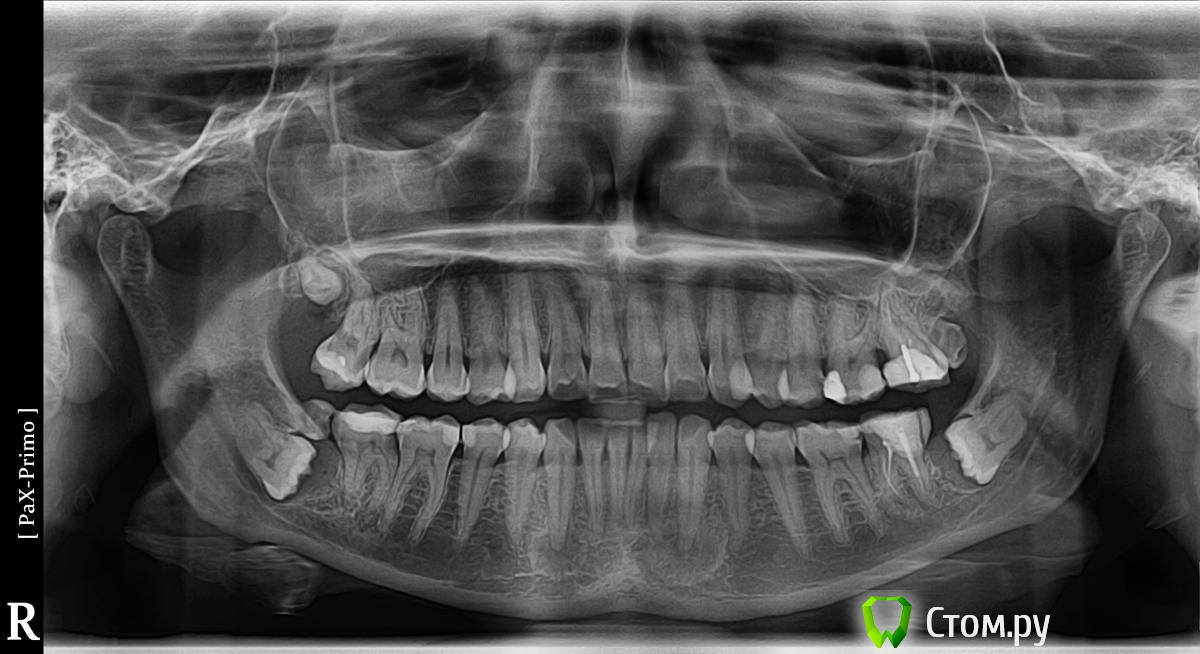

nata12 Опубликовано 7 февраля, 2014 Поделиться Опубликовано 7 февраля, 2014 Здравствуйте!Прошу совета.Весь прошлый год серьезно занималась зубами. Удалила 6 ретинированных зубов (у меня был сверхкомплект - 35 зубов), так же пришлось удалить 1-у семерку (там уже был кариес корня).После всех сложных удалений поставила 2 металлокерамические коронки - на верхнюю 6-ку и нижнюю 7-ку.2 раза делала панорамные снимки: в мае и в сентябре.И оба раза они показали одинаковую картину - какие-то круги вокруг корней нижних клыков.Стоматолог-хирург предположила, что это не кисты (т.к. края не ровные) и посылает в Стоматологический комплекс на Вучетича (Москва) для обследования - КТ или МРТ, биопсия и прочее.. Подозревает либо опухоль, либо просто такое специфическое строение.В общем по её словам - либо страшно, либо ничего страшного. Я сомневаюсь, ехать или нет.. Нижние клыки совершенно не болят и никогда не беспокоили. На Вучетича живая очередь и это куча потерянного времени и денег.. Травм не было. Несколько лет в детстве носила "пластинку" для исправления нижних зубов, но она не помогла (и не удивительно, т.к. как выяснилось у меня в челюсти места даже для 8-ок не было). Прилагаю снимок, это май 2013 года. На сентябрьском снимке всё то же самое, только нижних ретинированных зубов уже нет. А круги в десне вокруг клыков внизу точно такие же. Заранее спасибо за любое мнение по данной проблеме! Ссылка на комментарий